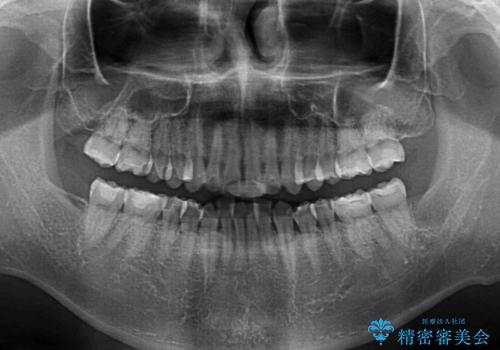

ディープバイトと叢生を解消 インビザライン矯正

- 前歯のデコボコを強い咬みしめを気にして来院された患者様です。

インビザラインを用いて、前歯の叢生を解消するとともに、ディープバイトを改善していくこととしました。

ディープバイトが改善されたことで、顎への負担が軽減され、更には上顎前歯の突出感も改善することができました。